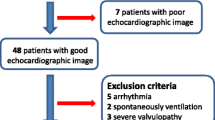

A total of 42 critically ill patients were assessed for enrolment in this study. Among them, 14 patients (33.3%) were excluded due to inability to acquire a high-quality image from the parasternal long-axis view to measure LVOTd or apical 5-chamber view to measure VTI. An additional eight patients (19%) were excluded due to atrial fibrillation (n = 5), aortic valve disease (n = 2), or technical difficulties in obtaining the PAC-CO measurement (n = 1).

Data were analyzed from 20 subjects [mean age 67 (± 14) years), 70% males]. Baseline characteristics of the study population are shown in Table 1. Briefly, the most common diagnosis for ICU admission was septic shock (45%). The majority of patients were receiving mechanical ventilation (90%) and vasopressor medications (80%).

Compared to included patients, the excluded patients had a faster heart rate and required higher norepinephrine doses. Variables associated with inability to acquire high-quality echocardiographic views were an abdominal wall dressing (p = 0.043) and high tidal volumes (p = 0.008) (Table 2).